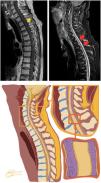

Sagittal T1 before (top left) and after contrast (top right). Sequences with diffuse and thick leptomeningeal enhancement involving the spinal cord. At the bottom, a graphic representation of the magnetic resonance imaging (MRI) findings with infiltration of the leptomeninges around the spinal cord.

Graphic representation (left) from the Axial T1 after contrast (right) magnetic resonance acquired in the same patient. The representation illustrates the leptomeningeal neoplasic infiltration enhanced by contrast in T1 sequences that was confirmed to be by plasmocytes with atypical morphology (enlarged cells, loose chromatin and evident nucleoli), a rare recurrence of multiple myeloma.